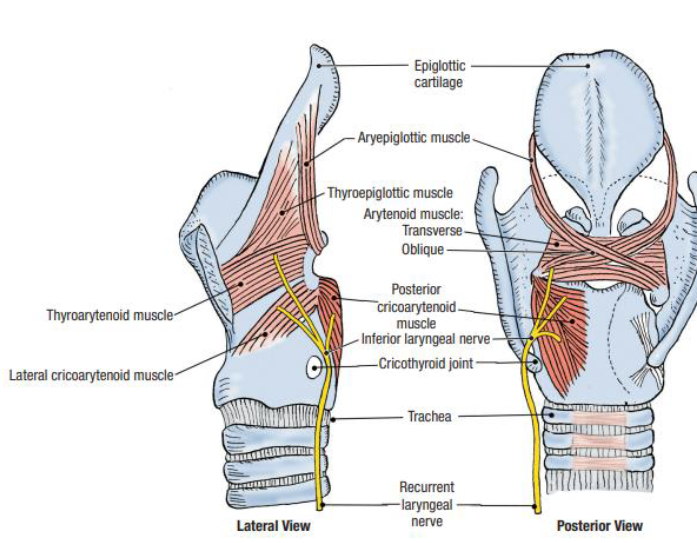

Muscle

關閉 Epiglotticus

- Thyroepiglotticus m

- Aryepiglotticus

Vocal fold

Motor: Recurrent laryngeal n.

- Arytenoid m.

- Transverse fiber / Oblique fiber

- Vocal fold adduction

- Post. cricoarytenoid

- Vocal fold abduction

- Lateral cricoarytenoid m.

- Vocal fold adduction

- Thyroarytenoid m.

- Arytenoid cartilage 往前

Motor: External laryngeal n.

- Cricothyroid m.

Nerve

- Sup. laryngeal n.

- Internal br.(Internal laryngeal n.)

- Sensor

- 穿過 Thyrohyoid ligament

- External br.

- Motor

- Internal br.(Internal laryngeal n.)

- Recurrent laryngeal n.

- Inf. laryngeal a.伴行

- 過Cricothyroid joint改叫Inf. laryngeal n.